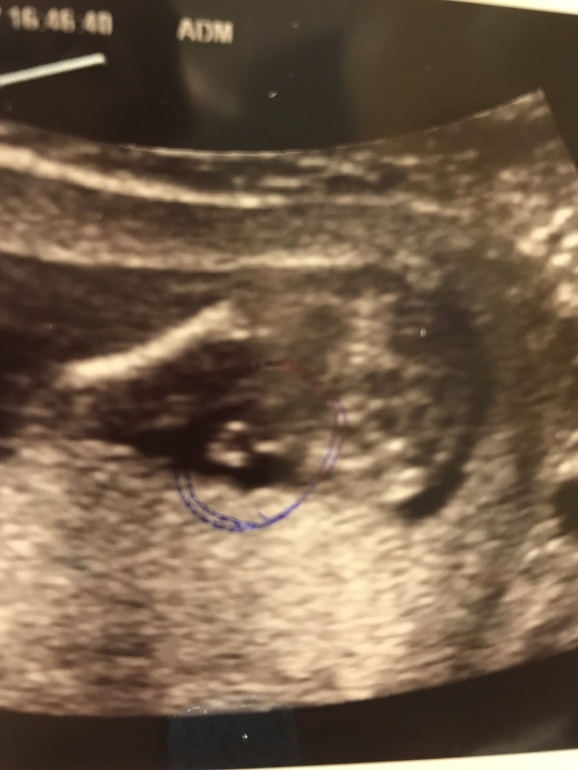

УЗИ, КТГ, доплерЯ понимаю, что малыш - это радость, но я реву 😭😭😭😭😭 Я была на 90% уверенна, что дочка

И вам прям показывали причендалья?? Или ребеночек прятал до 24 недель??? Мне узист сказала 90% малчик!! И 10% у меня осталась надежда...